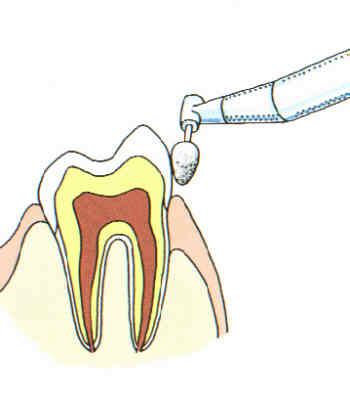

Zahnpolitur

Nach der Zahnsteinentfernung werden die Zähne poliert, um neuer Zahnsteinbildung möglichst wenig Ansatzstellen zu bieten.